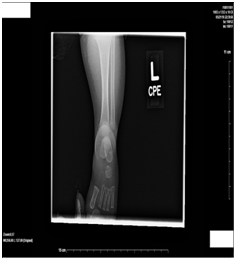

Blood cultures were drawn which were pending at the time of diagnosis but showed no growth after 5 days. Plain radiographs were ordered of the ankle (Figure 1) (Figure 2), knee (Figure 3) (Figure 4), and tibia/fibula (Figure 5) (Figure 6) to which showed no evidence of fracture or malalignment. Arterial and venous ultrasounds of the lower extremities also did not show compromise of the tibial or dorsalis pedis artery or vein. Finally, nonvascular ultrasound of his lower extremity demonstrated a complex fluid collection within the left upper calf posteriorly, measuring 1.9 x 2.7 x 3.7cm which appeared to involve the calf musculature (Figure 7).

Figure 5 Plain radiograph of left tibia/fibula, lateral.

Figure 6 Plain radiograph of left tibia, fibula.